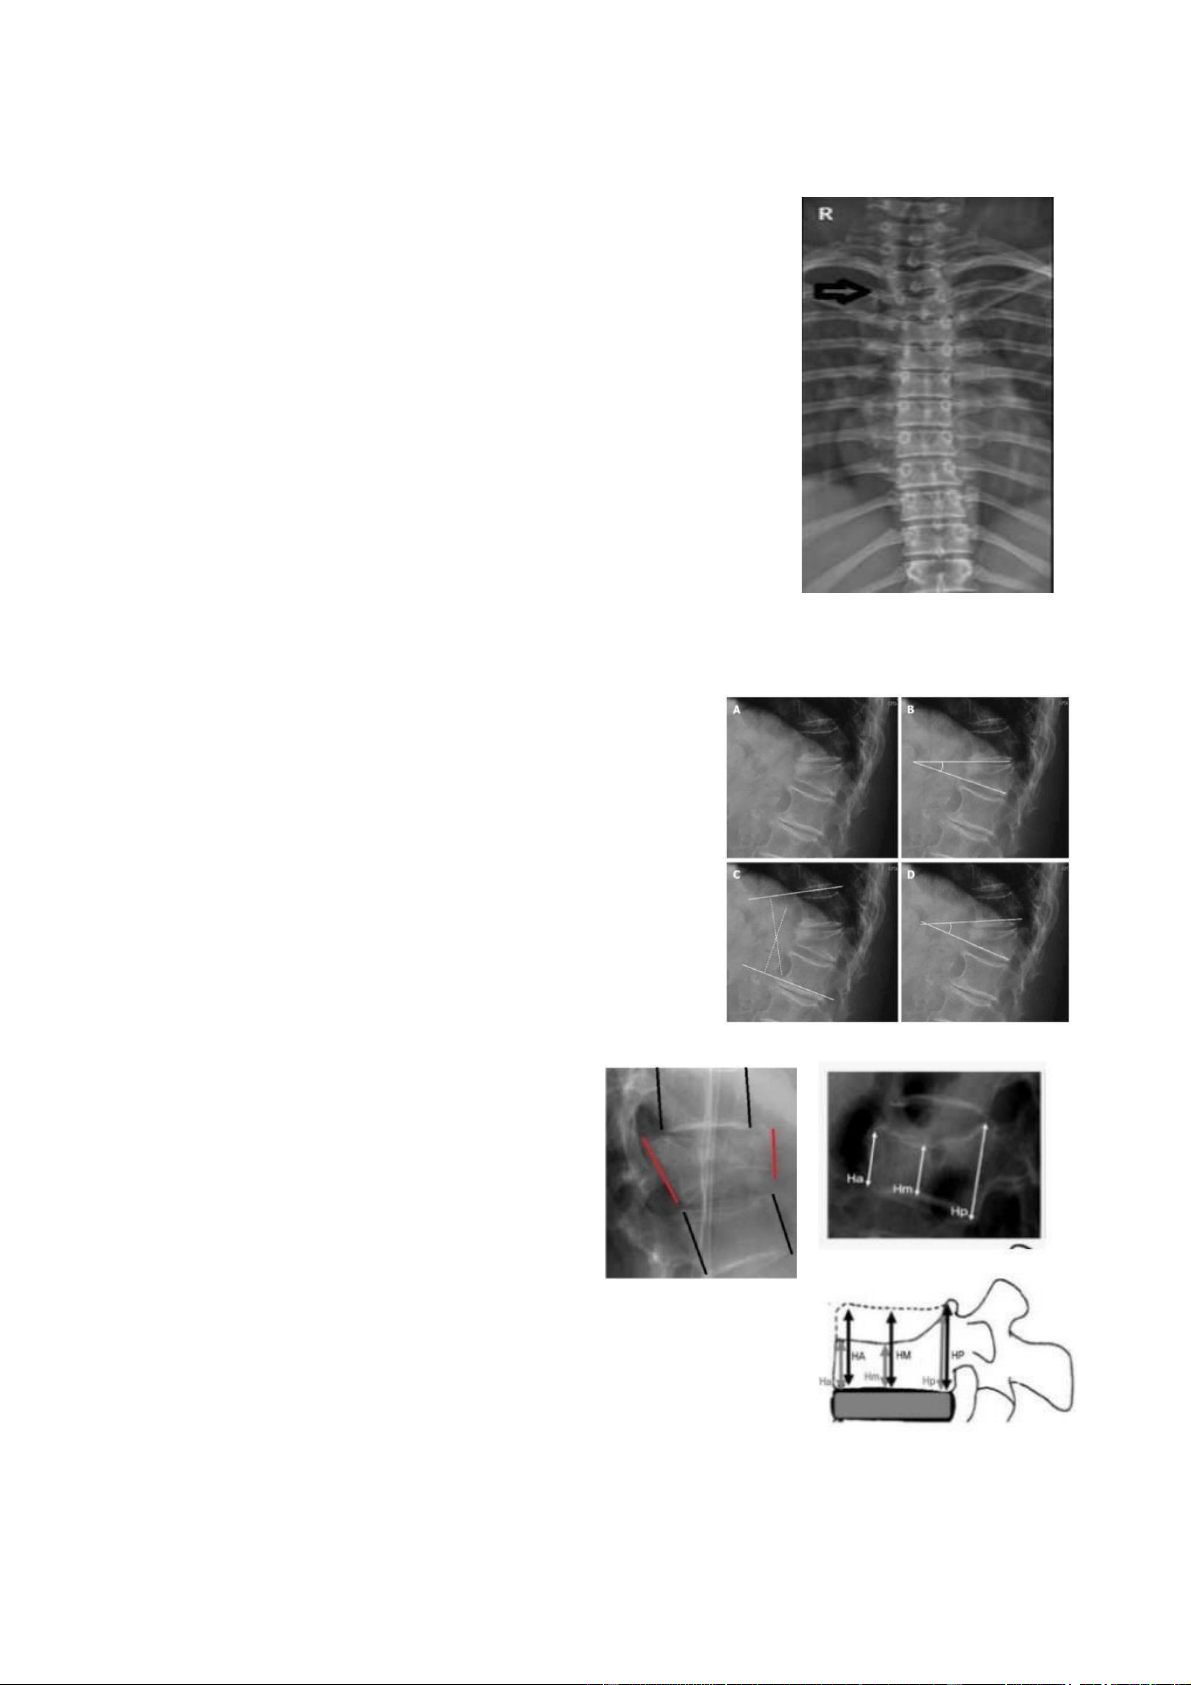

5.2. Chẩn oán hình ảnh • X quang qui ước Nguyên tắc: lOMoAR cPSD| 22014077

- Nếu chụp tốt, úng nguyên tắc thì 80 – 90% thấy ược

thương tổn bằng chụp X.Quang qui ước.

- Chụp phim thẳng, nghiêng và chếch 3/4 ể tìm thương tổn xương.

- Phim chụp phải thấy ược các ốt sống từ D1- L2.

Các yếu tố cần nhận ịnh là:

- Đường cong sinh lý và sự liên tục của cột sống.

- Trạng thái của các ốt sống, trục cột sống.

- Chiều dày của ốt sống, khoảng cách giữa các khớp.

- Xác ịnh vị trí tổn thương. - Góc gù thân ốt và góc gù chấn thương.

Trên phim nghiêng ánh giá: - Tình trạng gãy xương. - Xẹp thân ốt sống. - Trượt ốt sống.

- Gập ưỡn cột sống (ưỡn gù thân ốt

và gập góc vùng chấn thương).

Trên phim thẳng ánh giá: - Độ mở

rộng cuống sống - Lệch trục các

mỏm liên gai. - Hẹp khe liên ốt. -

Lệch trục và xoay cột sống. Các ánh giá khác:

- Chiều cao thành trước, thành sau và thân sống. - Khe sáng của ĩa ệm.

- Trật và gãy mỏm khớp, gãy cung

sau - Tình trạng mỏm gai và khoảng cách giữa chúng. lOMoAR cPSD| 22014077

- Khoảng cách giữa hai mắt sống tại vị trí tổn thương.